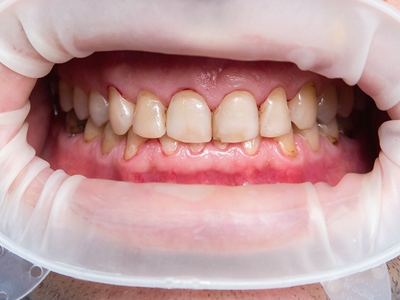

牙龈退缩牙齿出现三角形牙缝图

牙龈退缩表现为上排切牙、尖牙处牙龈发生回缩,导致牙龈暴露,并且牙齿发生松动,牙缝增大呈三角形,伴有口臭、牙根面敏感等症状。